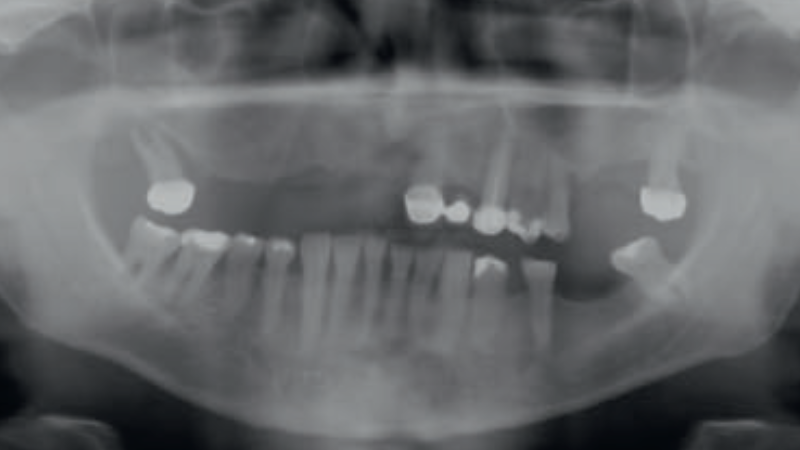

- Opis przypadku: Pacjent, lat 48, ogólnie zdrowy, bez przeciwwskazań do leczenia implantoprotetycznego, zgłosił się skierowany przez lekarza prowadzącego celem kompleksowej rehabilitacji protetycznej.

Metodologia: Pacjent, lat 48, z uzębieniem resztkowym w [...]